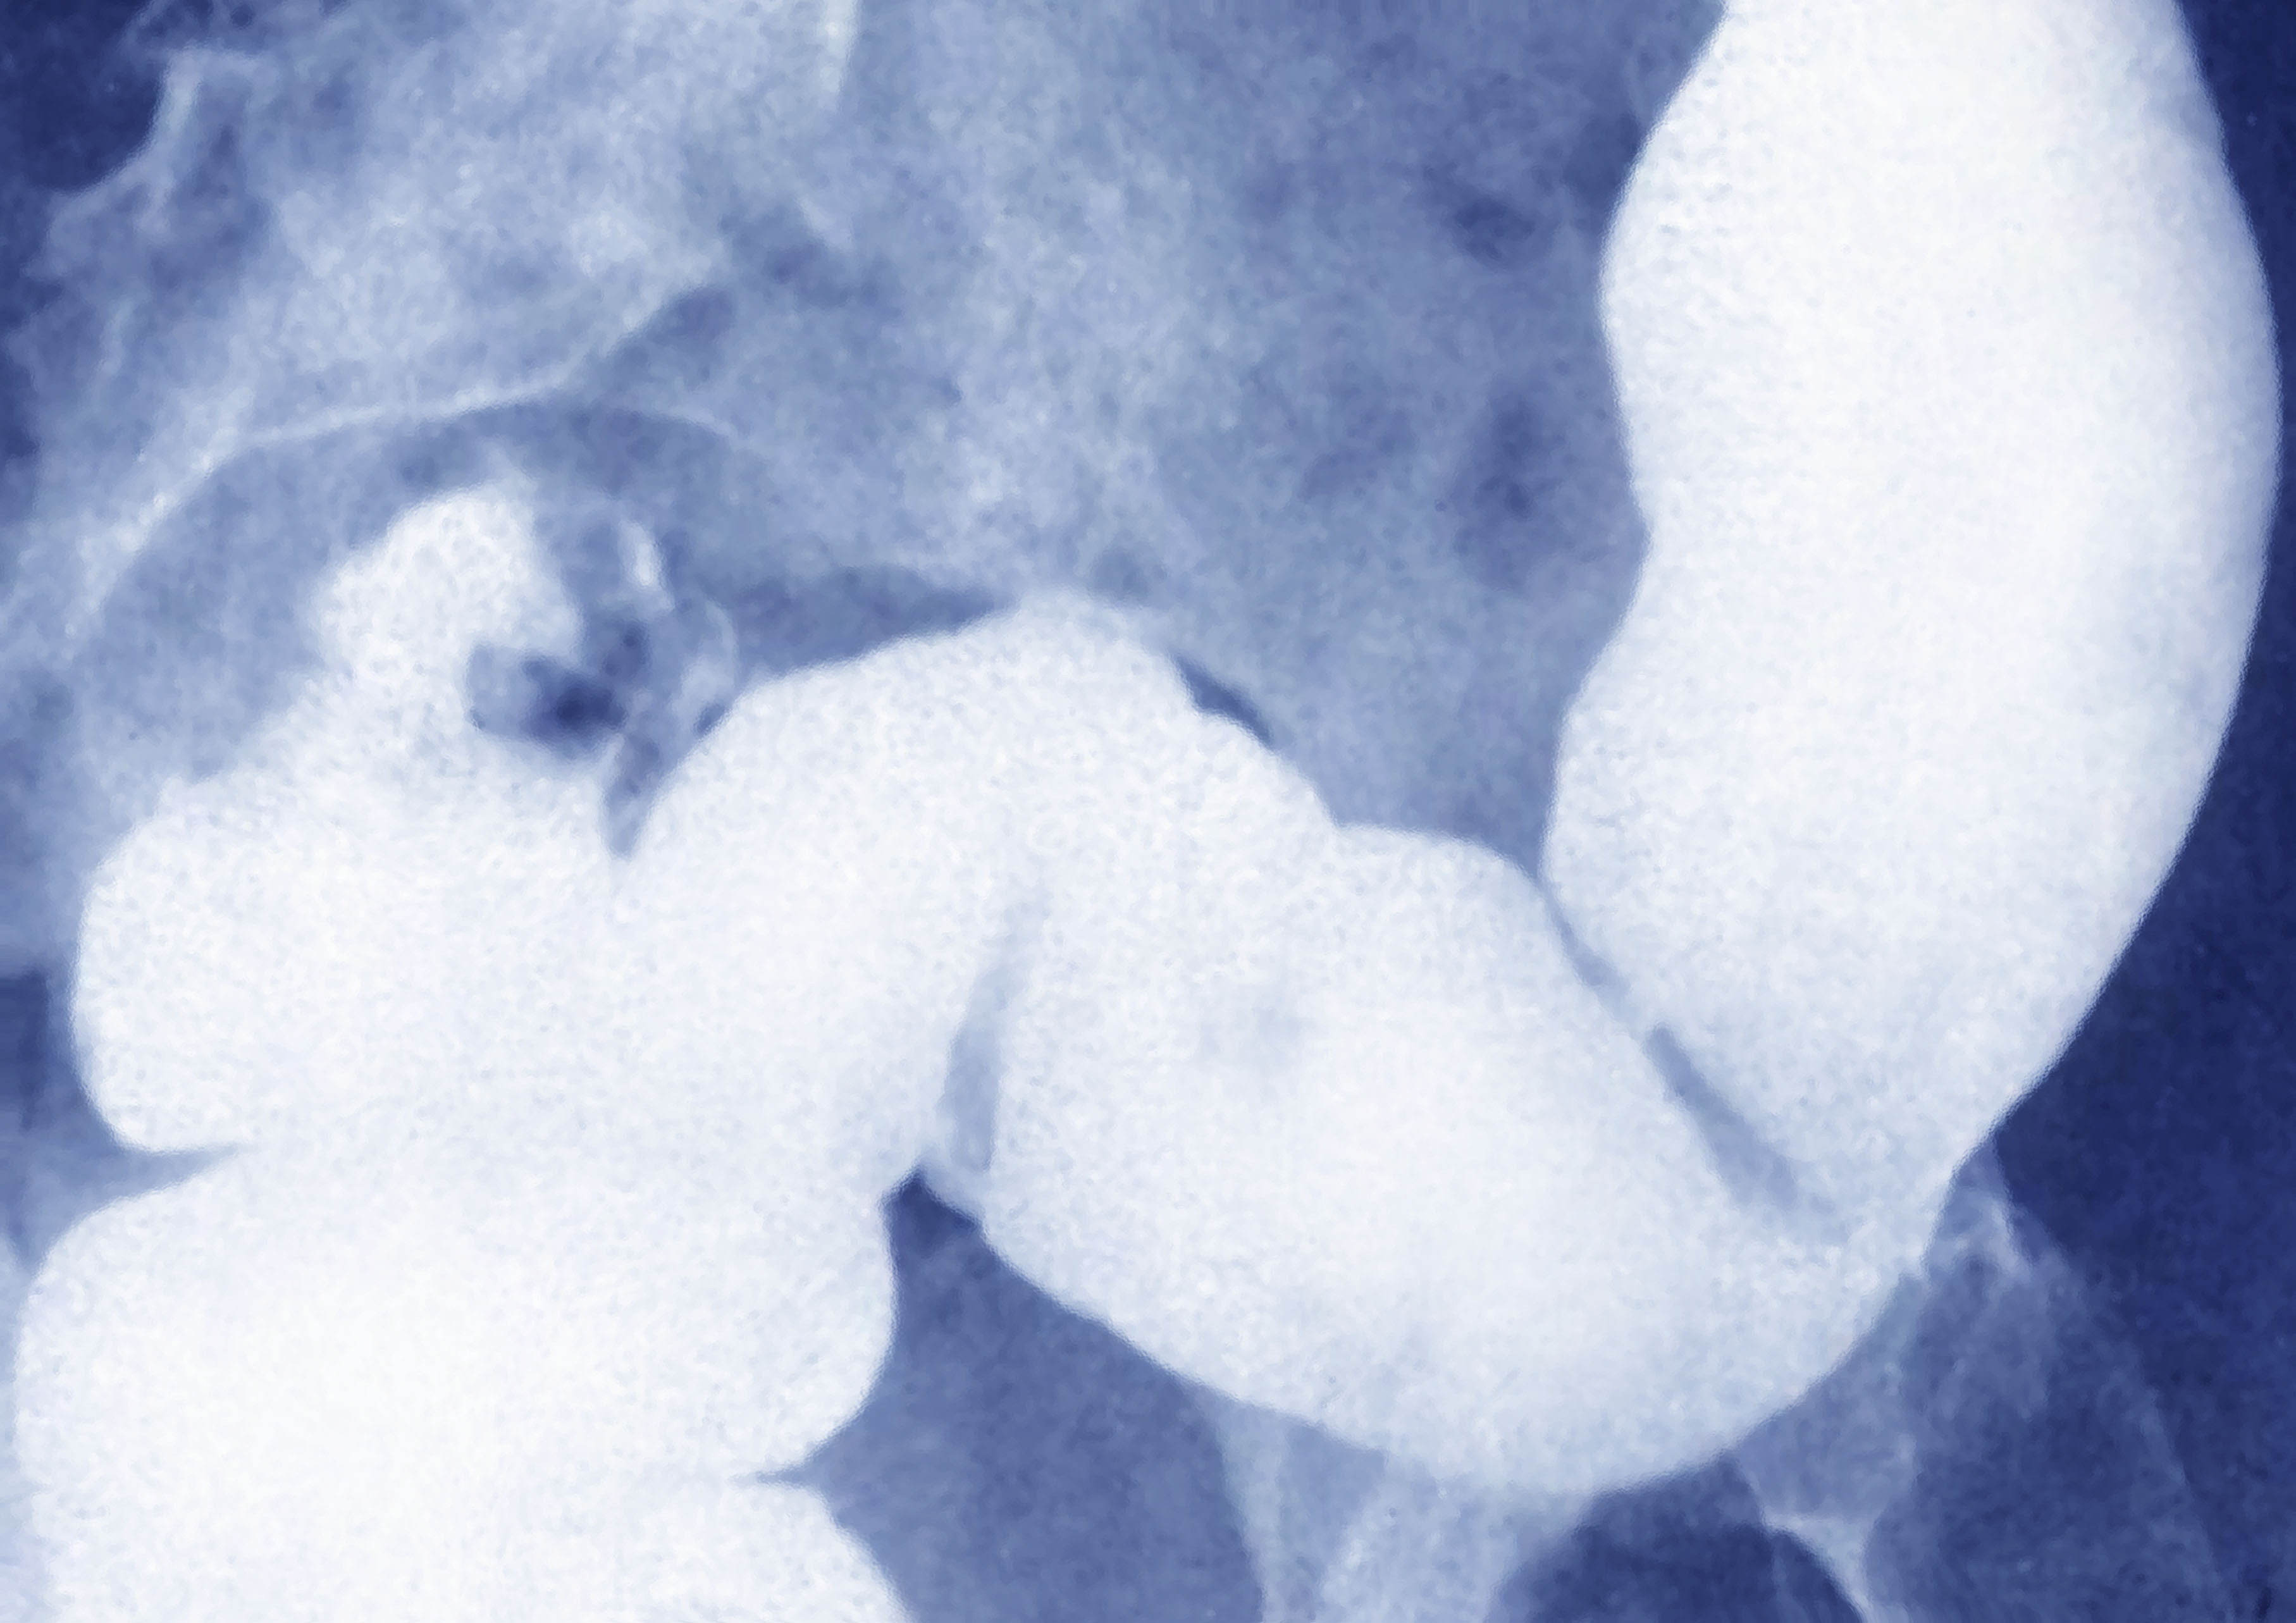

După ce a experimentat dureri abdominale și a avut analize de sânge anormale, Emma Dimery a făcut o colonoscopie, care a relevat o tumoare de „dimensiunea unei mingi de tenis” și alta „de dimensiunea unei mingi de golf”, a declarat ea pentru Fox News Digital.